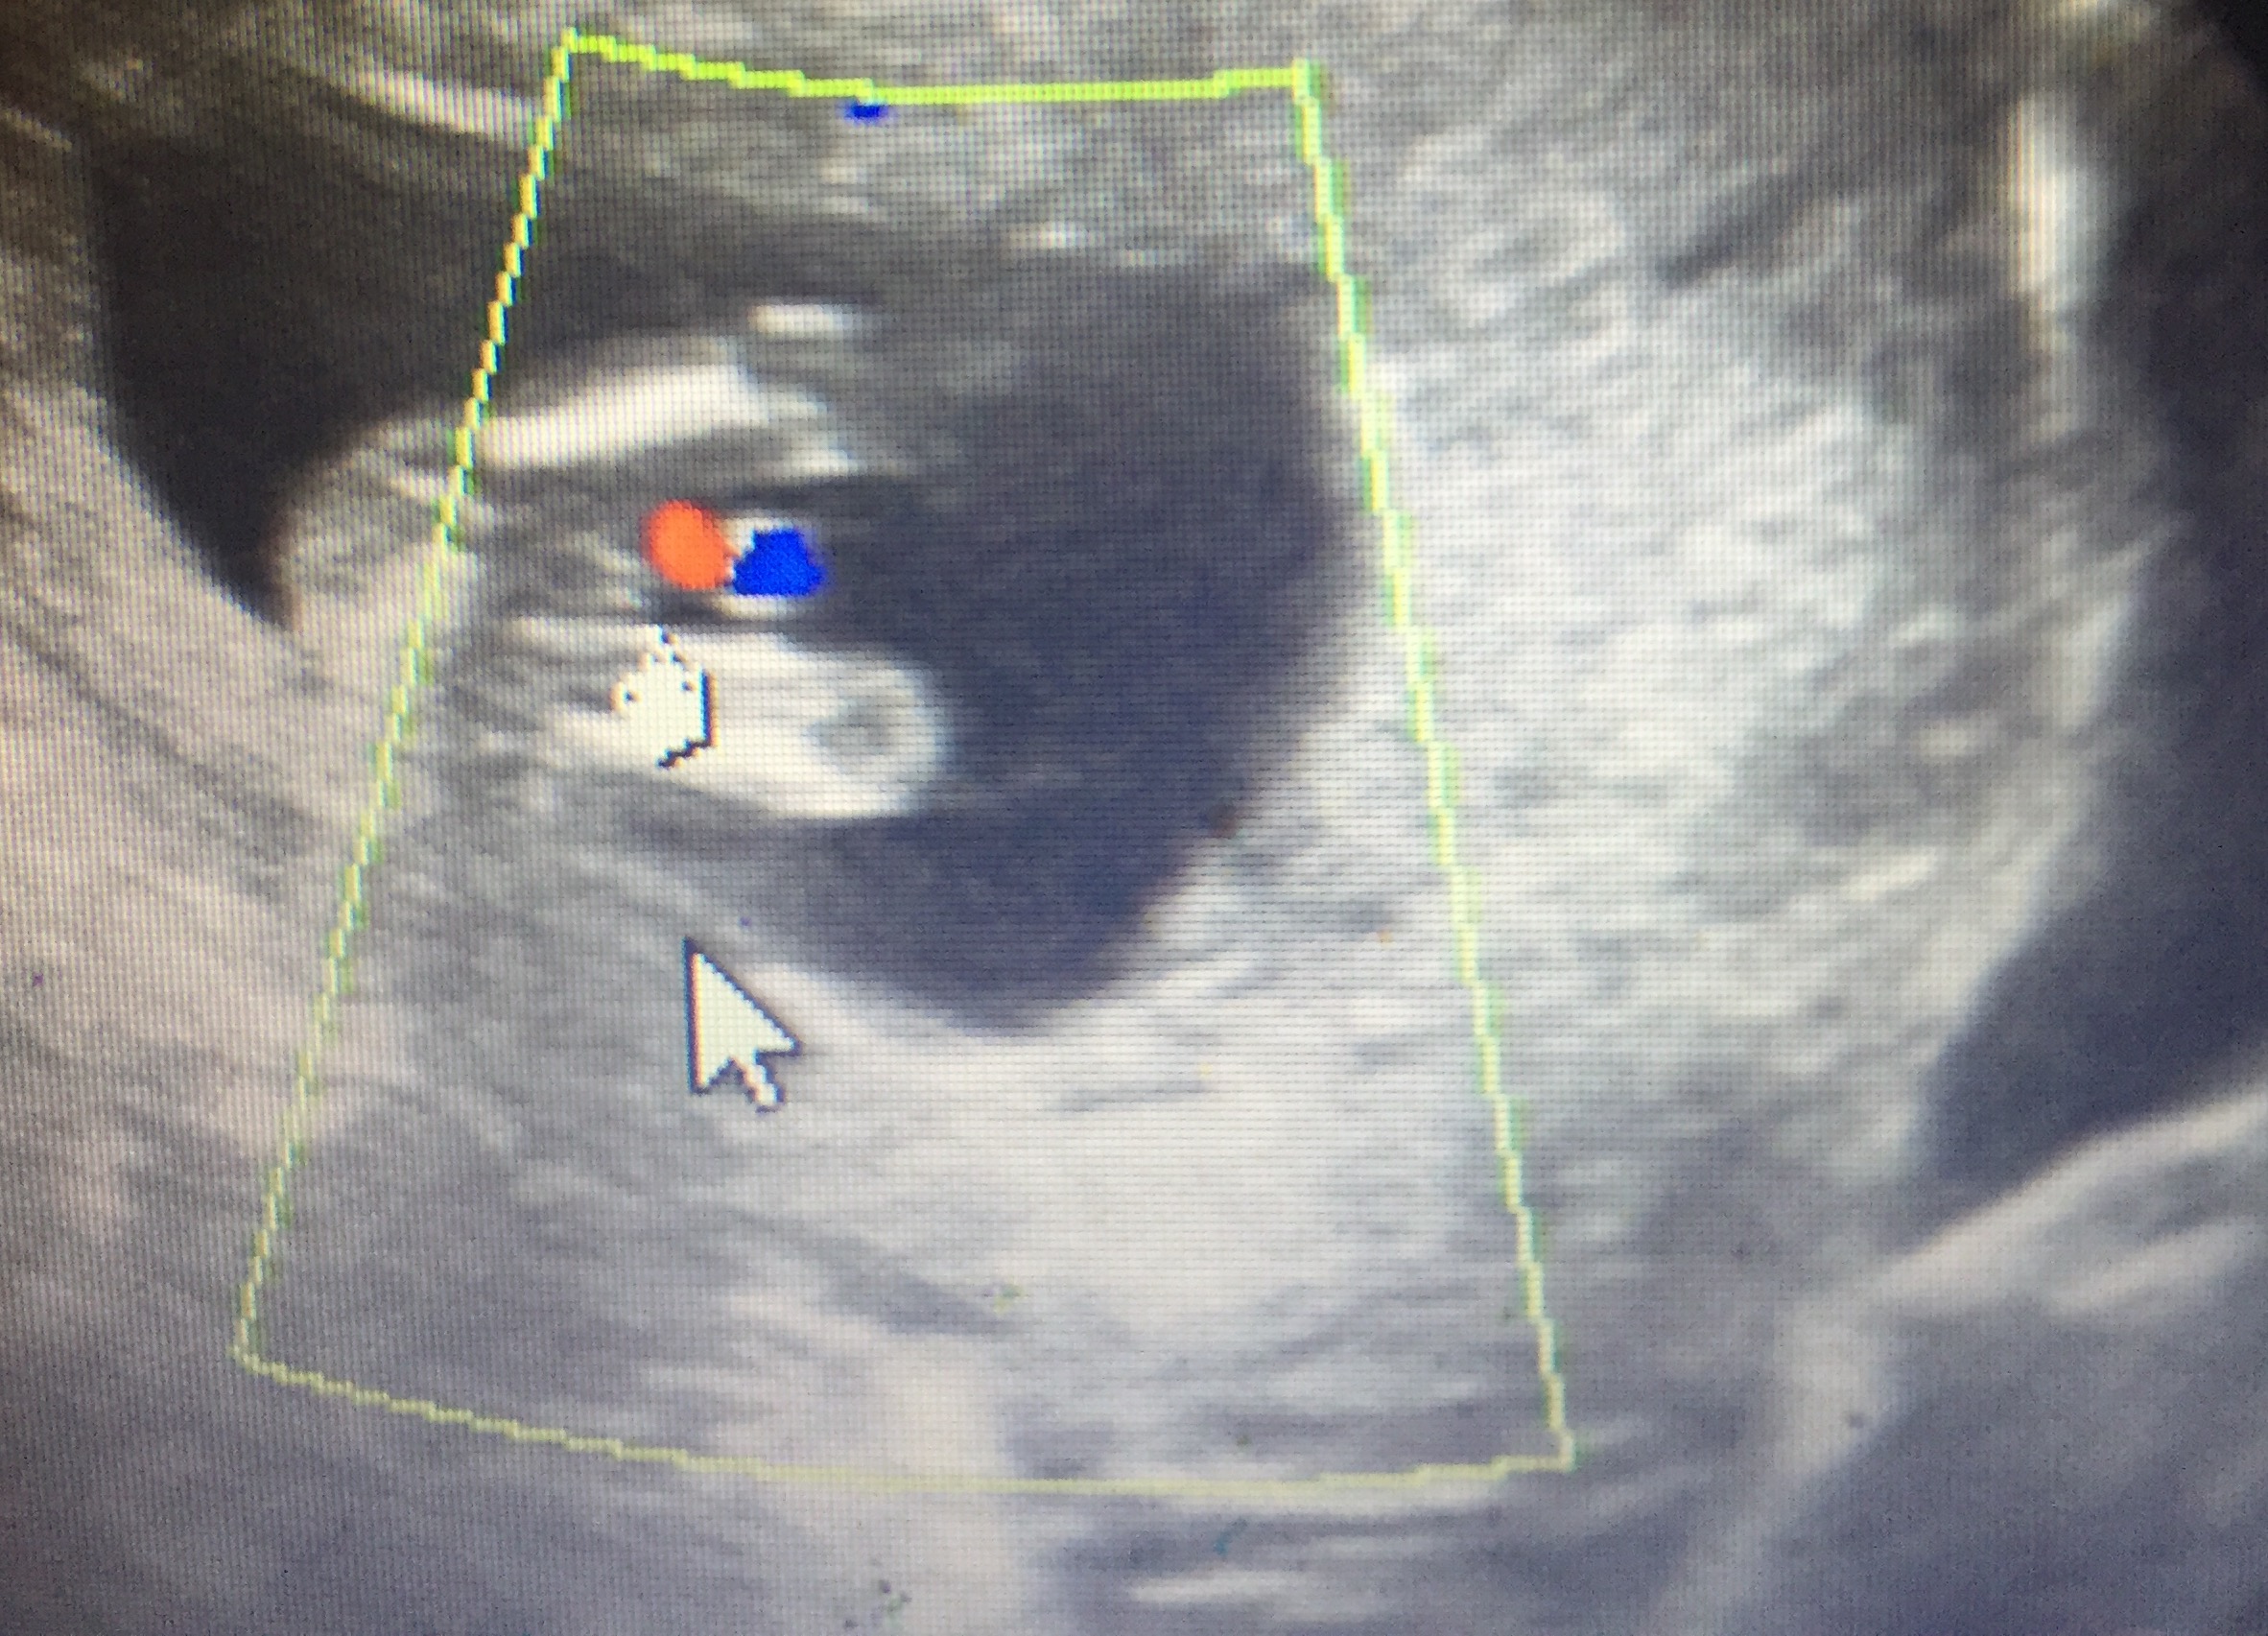

Told Boy at 13 weeks & told Girl at 16 weeks

went to an elective ultrasound at 13/14 weeks and was told boy but the Cord was between the legs and what she said was to be a "penis" seems way too long and it is also divided like a girl part. I have two boys already and their ultrasounds look completely different. After going to the elective ultrasound I saw my doctor at 16 weeksinformed us it was a girl and based off of the earlier ultrasound he gave us it looks girl also. Both my boys at 12 weeks were clear as day and this time my 13 week ultrasound from doctor had nothing between the legs.

I think the elective u/s gave us the wrong determination. Could this be a girl with swollen parts or cord over the girl parts? Attachment 28204Attachment 28205Attachment 28206Attachment 28207Attachment 28208